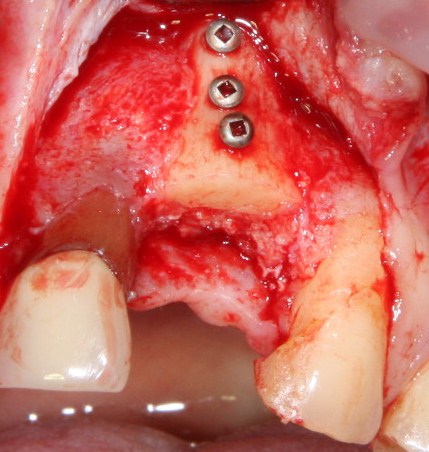

Я планирую установить имплантат Dentsply Friadent XiVE диаметром 3.8 и длиной 13 мм. Это оптимальный размер импланта для протезирования боковых резцов.

Установка импланта:

Убираем имплантодержатель. Обратите внимание, что полированная фаска вокруг шейки импланта находится над уровнем костной ткани. Чрезмерное погружение импланта — весьма распространенная имплантологическая ошибка.

Заглушка: